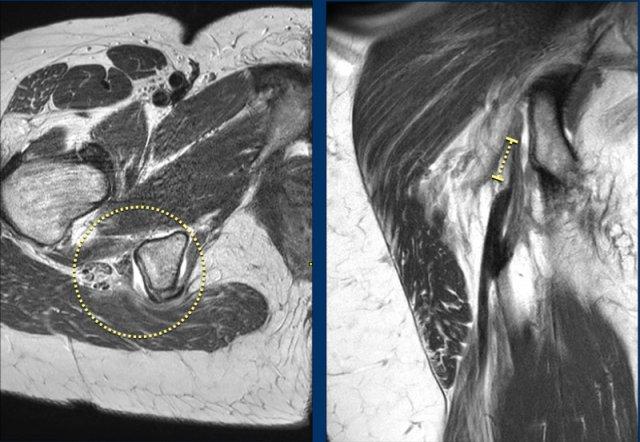

Ở bệnh nhân này, cả gân cơ bán màng bên phải lẫn gân chung đều bị bong.

Cả hai viên kem đều đã rơi.

Trên các hình ảnh này ghi nhận tổn thương toàn bộ chiều dày.

Cả hai viên kem đều rơi trên ảnh axial, cho thấy cả hai gân đều bị bong.

Trên ảnh coronal, tổng mức độ co rút đã được đo và ghi nhận.